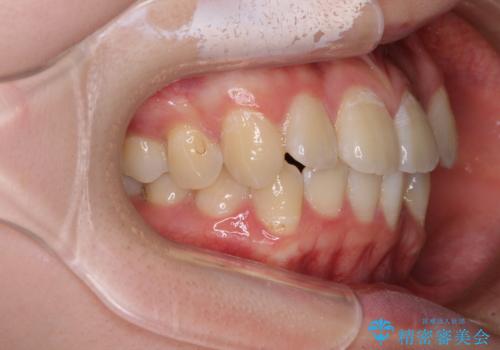

- 前歯のデコボコと八重歯を気にして来院された患者様です。

インビザラインでの治療を希望されていましたが、前歯のクロスバイトや下顎小臼歯の捻転が認められたため、インビザライン単独で治療を行うよりも、ワイヤー装置を併用した方が、治療期間の短縮やトラブル回避できると判断し、ワイヤー装置を併用することとしました。

まずはワイヤー装置により前歯のクロスバイトと下顎小臼歯の捻転を改善し、その後インビザラインにより全体を整える矯正治療を行うこととしました。